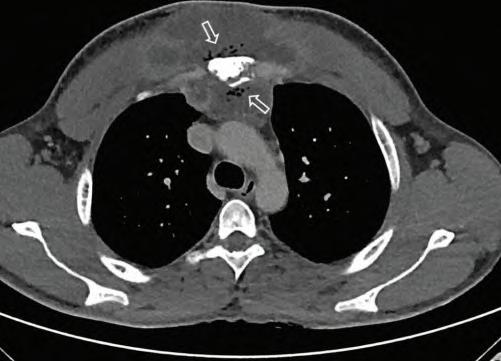

CFig.1.6 Computedtomography(CT)scanofapatientwithanteriorchestwallpain.CTscanningof anterioruppermediastinalmassafteriodinatedcontrastadministration.Lungwindow(A). Mediastinumwindow(B)showsinhomogeneouscontrastenhancementofthemass.Enhanced multidetectorCTfollow-upafter3months(C)showsdecreaseinvolumeofmediastinalmass. (FromDeFilippoM,AlbiniA,CastaldiV,etal.MRIfindingsofTietze ’ssyndromemimickingmediastinalmalignancyonMDCT. EurJRadiolExtra .2008;65(1):33 35[Fig.1].ISSN1571-4675, https:// doi.org/10.1016/j.ejrex.2007.10.006, http://www.sciencedirect.com/science/article/pii/S1571467 507000892.)

Plainradiographsareindicatedforall patientswhopresentwithpainthatis thoughttobeemanatingfromthecostosternaljointstoruleoutoccultbony disorders,includingtumor( Fig.1.5 ).Iftraumaispresent,radionuclidebone scanningmaybeusefultoexcludeoccultfracturesoftheribsorsternum. Basedonthepatient ’ sclinicalpresentation,addi tionaltestingmaybeindicated,includingacompletebloodcount,pr ostate-specificantigenlevel,erythrocytesedimentationrate,andantin uclearantibodytesting.Laboratory evaluationforcollagenvasculardiseaseisindicatedinpatientssufferingfrom costosternaljointpainifotherjoin tsareinvolved.Computedtomography

(CT)scanning,magneticresonanceimag ing(MRI),andultrasoundimagingof thejointsareindicatedifjointinstabilityoroccultmassissuspected,ortoelucidatethecauseofthepainfurther( Figs.1.6,1.7 ,and 1.8 ).Injectionofthe costosternaljointcanserveasbothadi agnosticandatherapeuticmaneuver ( Figs.1.9 and 1.10 ).